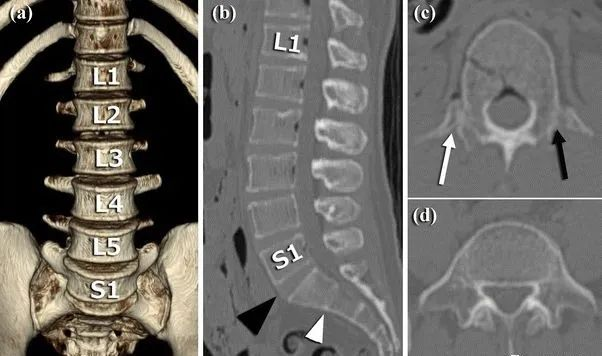

1984年,Castellvi提出LSTV分类系统将移行椎分为Ⅰ-Ⅳ型。

Ia型(单侧)和Ib型(双侧):横突肥大宽度超过19mm

IIa型(单侧)和IIb型(双侧):横突与骶骨相接触形成假关节

IIIa型(单侧)和IIIb型(双侧),横突与骶骨发生骨性融合

IV型:一侧横突与骶骨形成假关节,另一侧形成骨性融合

目前,腰骶移行椎以Castellvi的分类方法最为常用。其主要根据横突形态及其与骶骨、髂骨是否融合或形成假关节而分为4型,Ⅰ、Ⅱ、Ⅲ型又根据单、双侧分为A、B两个亚型。